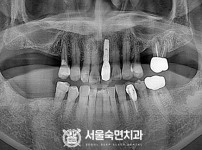

임플란트-전후사진1

임플란트-전후사진2

치과를-선택할-때-꼭-확인하세요-서울숙면치과-임플란트-전후사진